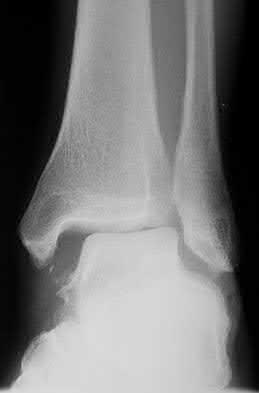

1011) The radiograph seen in Figure 67 reveals an ankle fracture in a 65-year-old woman who slipped on the ice. She has a history of diabetes mellitus for the past 7 years and reports that she maintains fair control of her diabetes; her last HgbA1c was 8%. The patient is a community ambulatory who lives independently. Examination reveals she has absent sensation with the 5.07 monofilament. When determining management, the physician must consider which of the following?

5. Early mobilization and weight bearing to minimize stiffness Corrent answer: 1

Increased immobilization and delayed weight bearing are indicated in the neuropathic population after treating an ankle fracture. Patients with diabetes mellitus and peripheral neuropathy have higher complication rates following ankle fractures treated surgically or nonsurgically. The elevated HgbA1c and

neuropathy both predict a higher complication rate with this fracture. Outcomes after nonsurgical management of this fracture are poorer than after surgical treatment. Early bone grafting is not recommended in closed fractures, but the use of supplemental internal fixation is recommended because of the high risk of nonunion. More substantial constructs with supplemental fixation, locking fixation, fixation through the calcaneus and talus into the tibia, or external fixation are necessary. Primary arthrodesis is not recommended in this fracture pattern or in a relatively active patient.